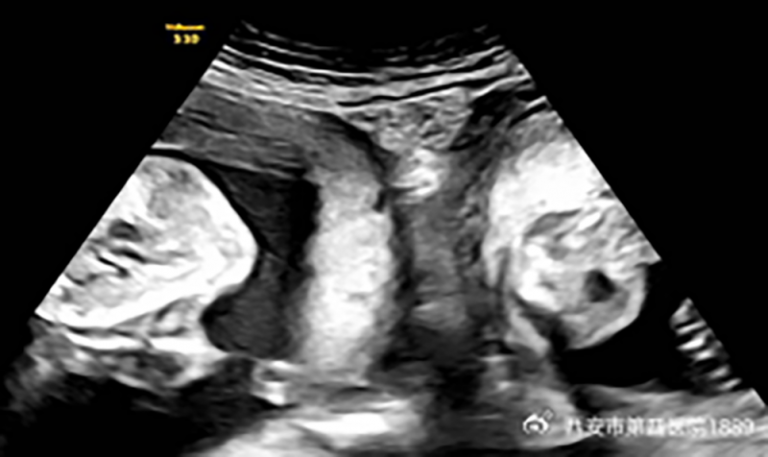

But in January, Li became pregnant again and discovered during an early ultrasound that she was expecting not just one child but twins – one in each womb.